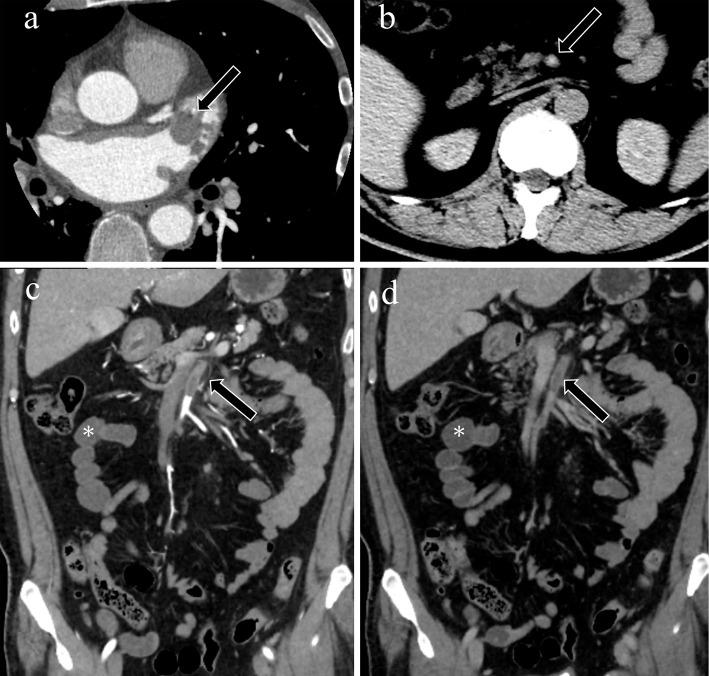

Acute mesenteric ischemia is a life-threatening condition. A comprehensive approach involving a multidisciplinary team to review patient background, clinical history, physical examination, laboratory data, and imaging examination for respective diagnosis of superior mesenteric arterial occlusion, nonocclusive mesenteric ischemia, and superior mesenteric venous occlusion is essential. The most important imaging modality is computed tomography, which is used for diagnosis and for directing therapeutic strategy (e.g., endovascular revascularization, surgical bowel resection, or conservative management). Computed tomography image findings can support triaging of irreversible transmural bowel necrosis compared with reversible ischemic change with reperfusion. In this review article, the computed tomography imaging findings specifically associated with the pathophysiology of superior mesenteric arterial occlusion, nonocclusive mesenteric ischemia, and superior mesenteric venous occlusion are reviewed.

急性肠系膜缺血是一种危及生命的疾病。采用多学科团队的综合方法来审查患者背景、临床病史、体格检查、实验室数据以及影像学检查,以分别诊断肠系膜上动脉闭塞、非闭塞性肠系膜缺血和肠系膜上静脉闭塞至关重要。最重要的影像学检查方法是计算机断层扫描,它用于诊断并指导治疗策略(如血管内血运重建、手术肠切除或保守治疗)。计算机断层扫描图像结果有助于区分不可逆的透壁性肠坏死与可通过再灌注逆转的缺血性改变。在这篇综述文章中,将对与肠系膜上动脉闭塞、非闭塞性肠系膜缺血和肠系膜上静脉闭塞的病理生理学具体相关的计算机断层扫描影像学结果进行综述。